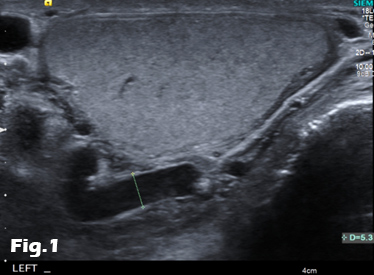

We present the case of a 59-year-old male, previously fit and well who presented to the General Practitioner with a 3 week history of epigastric pain, shortness of breath and unintentional weight loss. On examination, there was evidence of abdominal distension and palpable swelling of left testes. Initial investigation with US of the scrotum revealed dilated (maximally 5.3mm) left pampiniform plexus with retrograde flow on Doppler ultrasound and Valsalva manoeuvre, consistent with an extensive unilateral varicocele (Fig. 1 and 2). Subsequent abdominal ultrasound demonstrated moderate ascites, dilated common bile duct, large right sided pleural effusion and a large 14x14cm solid, vascular epigastric mass. This prompted urgent surgical referral and further cross-sectional imaging (Fig. 3). CT abdomen showed a large soft tissue density retro-peritoneal mass obliterating the portal mesenteric vein circulation and causing the left varicosity (Fig. 4). Ultrasound guided biopsy of the central abdominal mass confirmed a Stage IV Mantle cell Lymphoma.

Figure 4: Contrast-enhanced CT of the abdomen demonstrating the retro-peritoneal mass. Axial images (A, B) of the retro-peritoneal mass encasing the superior mesenteric artery. Sagittal reformatted image (C) of the retroperitoneal mass demonstrating the superior mesenteric artery encasement, the extent of the mass and pleural effusion. Coronal reformatted image (D) of the retroperitoneal mass. Note is made of fluid in the perihepatic space and within the pelvis.